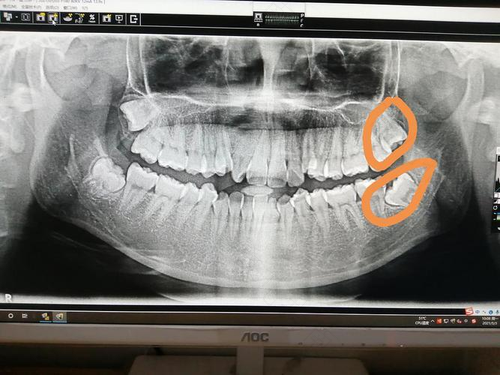

拔牙的话,孩子同一侧的两颗牙可以一起拔,如果没有在同一侧,最好先拔一颗,在一周以后再拔第二颗,但是也要看出血情况。如果牙比较难拔,而且出血量很多,就要暂停把第二颗牙了。如果恢复的好,可以拔第二颗牙。